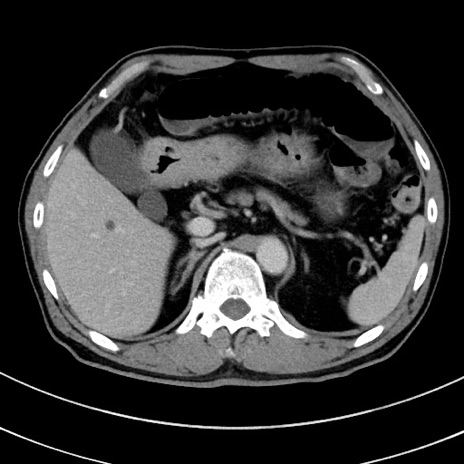

症例8(横断像)

【症例】 60歳代男性

【主訴】 黒色吐物

【現病歴】 4日前から嘔気自覚、2日前の朝食後にも嘔気あり、自分で手で嘔吐反射起こし嘔吐したところ血が混ざっていたため受診。

【既往歴】 5年前汎発性腹膜炎を伴う急性虫垂炎で手術、高血圧、前立腺肥大症、高脂血症

【身体所見】 腹部正中に手術癩痕あり 腹部平坦・軟圧痛なし膨満感あり

【データ】WBC 8400、CRP 4.54